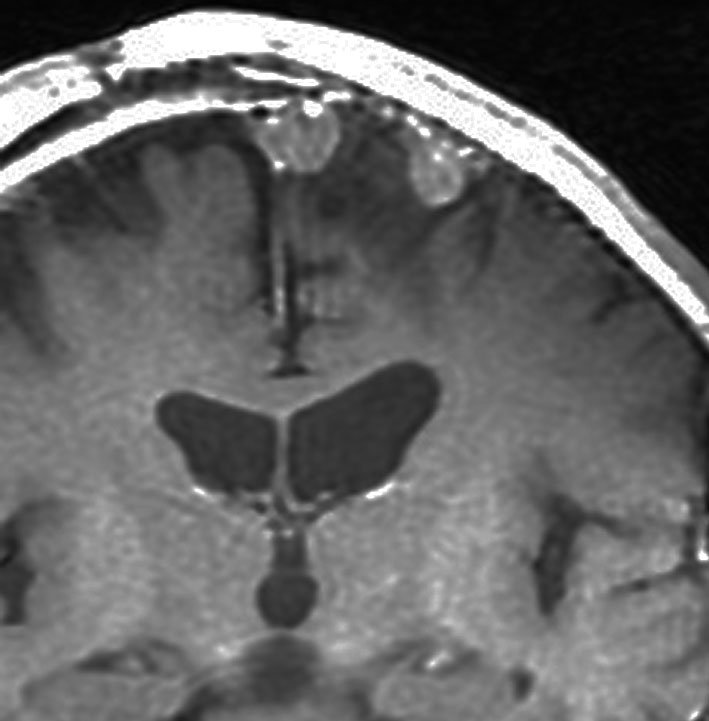

左は,造影剤を使ったガドリニウム増強MRIです。腫瘍が白く丸く見えます。右はフレア画像で,腫瘍の周囲の脳浮腫(脳のはれ)です。左前頭葉が,かなり強くはれています。この腫瘍は小さいのですが,脳のはれが強すぎるので手術摘出したほうがいいです。浮腫が悪化すると,てんかん発作や認知機能低下がでる可能性があります。